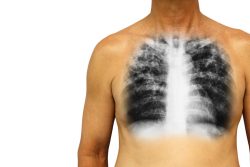

Инфильтрация легких – клинический синдром, при котором происходит замещение нормальной воздушности легочной ткани патологическим субстратом повышенной плотности, чаще всего воспалительного характера. При этом в паренхиме легких образуется участок, характеризующийся увеличенным объемом и повышенной плотностью, а также скоплением несвойственных ей клеточных элементов.